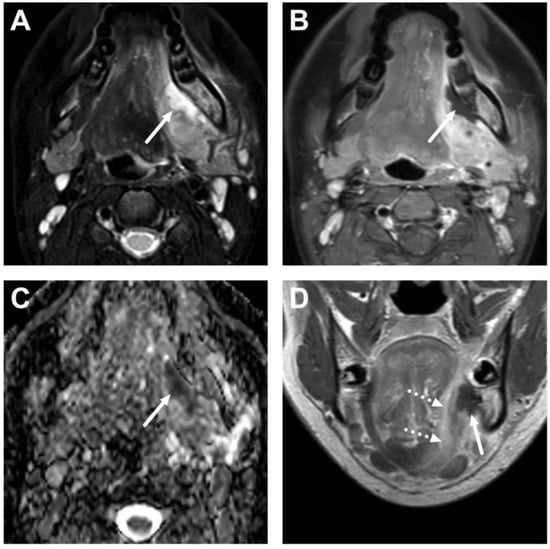

6.2. Venous Thrombosis